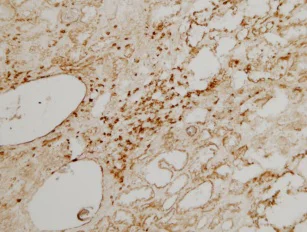

Immunohistochemistry (Frozen sections) - Anti-CD3 antibody (AB828)

• IHC-Fr

This immunoperoxidase picture shows inflammatory cell infiltration with many T-lymphocytes in the interstitium of human kidneys with congenital nephrotic syndrome of the Finnish type (CNF, NPHS1). Immunoperoxidase staining of frozen sections with ab828 antibody (oval shaped, unstained spaces on the left are glomeruli).

This image was kindly supplied as part of the review submitted by Arvi-Matti-Kuusniemi.